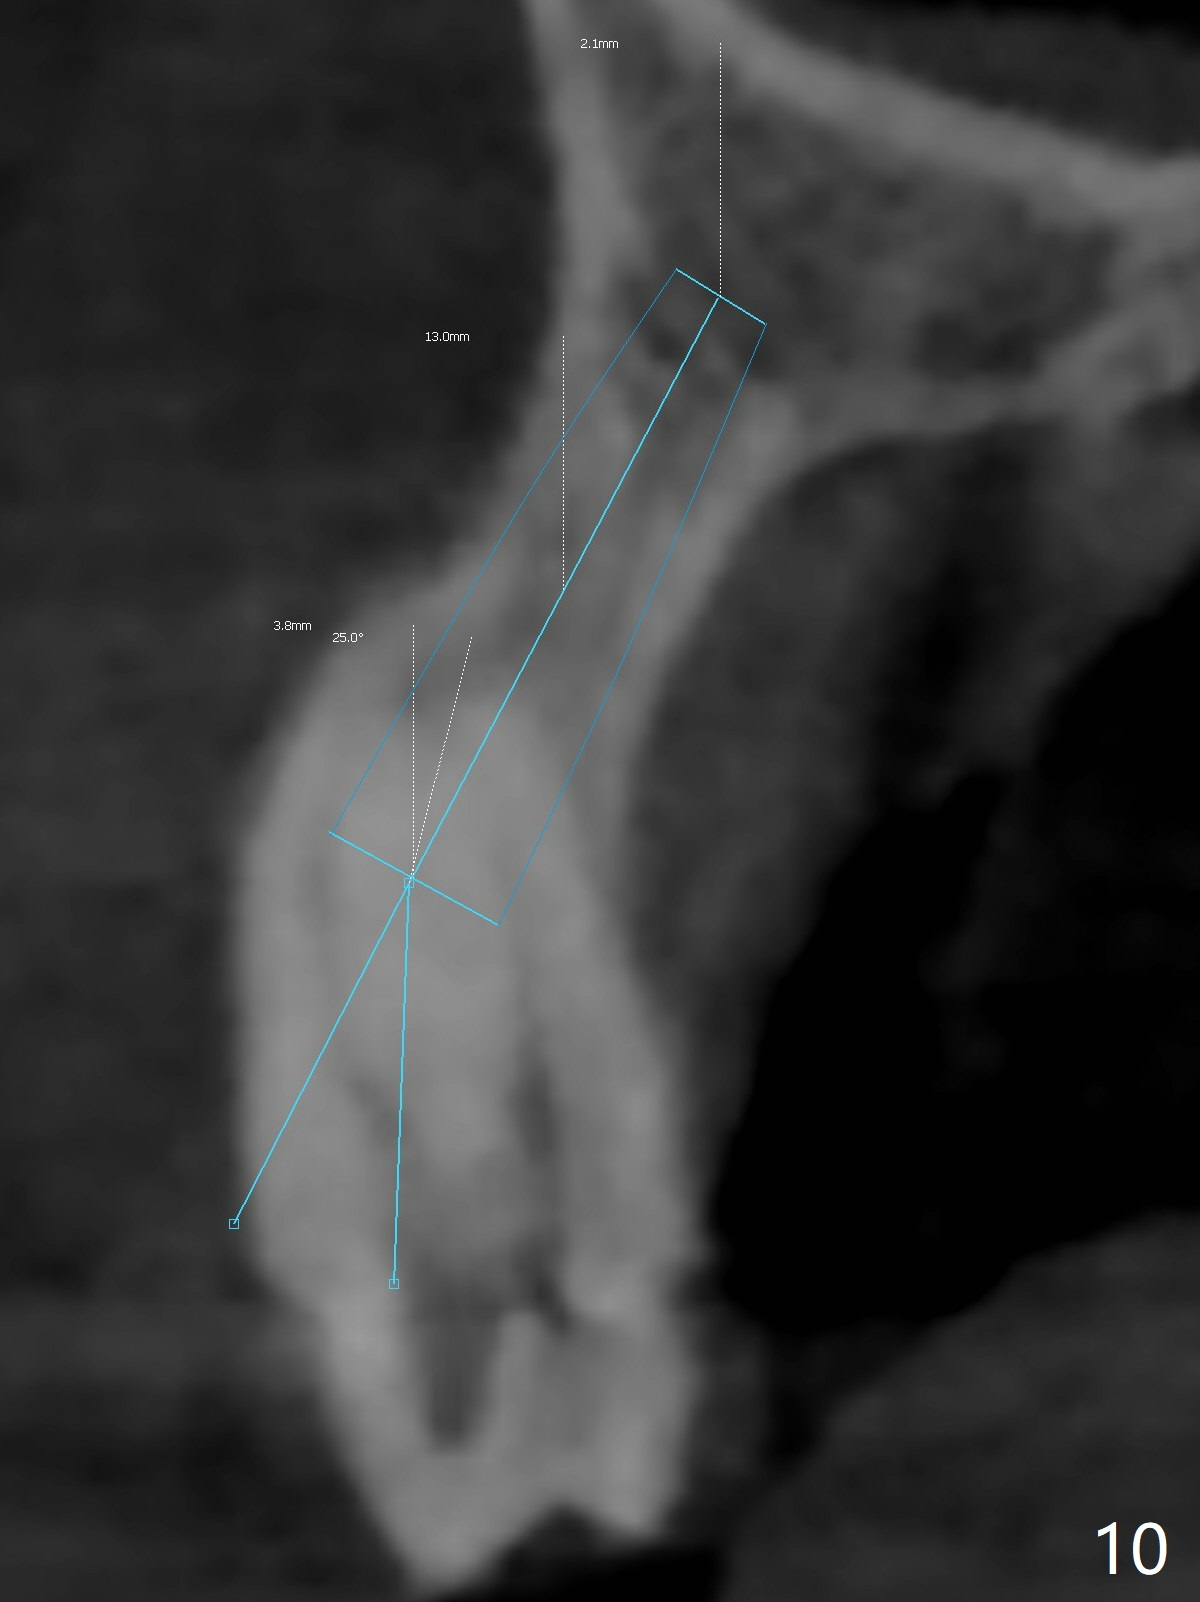

A 51-year-old woman lost the teeth #6 and 7 due to odontoma removal ~30 years ago. The area was restored with a FPD. The latter is removed with immediate implant at #8 8-9 months earlier. Particulate bone graft does not repair the bone deficiency at #6, 7 (Fig.2,3), although the soft tissue looks bulky (Fig.1). It appears that the palatal defect also needs a piece of bone block to fill in (Fig.4). The block will be harvested from the chin (Fig.5,6). If the block graft turns out to be impracticable, the periodontally compromised tooth #5 (bone loss, Fig.2,3,7) will be extracted for immediate implant. Initial osteotomy will be established in the palatal socket (Fig.8,9). Either a 2- (Fig.10) or 1- (Fig.11) piece implant will be placed. After wound healing, impression will be taken for a lab-fabricated provisional FPD.